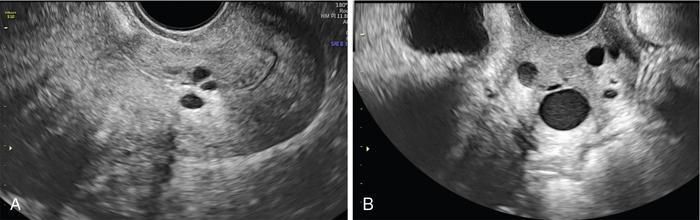

John De Lindsay, Usha Nandini Ganeshan, Vidya CERVICITIS Acute or chronic inflammation of cervix is termed as cervicitis. Noninfectious causes of cervicitis include trauma, pelvic radiation and chemical irritation. Most acute cervicitis is secondary to an infectious agent, commonly Trichomonas vaginalis, Candida albicans, herpes simplex virus, Neisseria gonorrhoeae and Chlamydia trachomatis. Patients usually present with purulent or mucopurulent cervical and vaginal discharge and may complain of pelvic pressure or discomfort. The cervix in patients with acute cervicitis shows a diffusely heterogeneous echotexture of the cervical mucosa and stroma, but the key finding is markedly increased vascularity on colour Doppler. Absence of mass is the differentiating feature between inflammation and malignancy. Free fluid can also be seen in the pouch of Douglas. CT may demonstrate an enlarged uterine cervix, an abnormally enhancing endocervical canal, and parametrial fat stranding. Retention cysts of the uterine cervix are termed as nabothian cysts. They are formed as a result of the healing process of chronic cervicitis. They are usually less than 1 cm, incidentally detected at imaging and are considered a normal finding in multiparous women. They may enlarge and become symptomatic because of mass effect, but this happens infrequently Majority of nabothian cysts, appear as small, simple anechoic cysts in the cervix, with no internal vascularity (Fig. 11.18.1.1). Their appearances can also vary depending upon any internal proteinaceous or haemorrhagic content, cyst clustering and deeper cervical stromal extension. US features that raise concern for malignancy include a solid component and marked vascular flow in the lesion at colour Doppler US. Tunnel cluster is a special variant of nabothian cyst with complex multicystic dilatation of the endocervical glands. Though macroscopically it resembles adenoma malignum, the epithelial cells of the tunnel cluster, do not show any cellular atypia similar to nabothian cyst. Nabothian cysts exhibit intermediate or slightly high signal intensity on T1-weighted (T1W) images and have prominent high signal intensity on T2-weighted (T2W) images. Presence of a solid component surrounding or separating the cysts gives us a clue to differentiate adenoma malignum from a benign nabothian cyst cluster. MR imaging also may be helpful in distinguishing adenoma malignum from benign multicystic lesions of the cervix. MR imaging features associated with malignancy include irregular margins, enhancing solid components, local invasion and metastases. CERVICAL STENOSIS Stenosis of the uterine cervix is the pathological narrowing of the cervix. The term cervical stenosis is clinically defined as cervical narrowing that prevents the insertion of a 2.5-mm-wide dilator. In utero exposure to diethylstilbestrol contributes about 20% of the cases. Often associated with endometriosis. Cervical stenosis in menopausal patient is asymptomatic. Retrograde menses may occur in women of reproductive age, thus posing a risk of endometriosis. Dysmenorrhea is present in up to 50% of patients with cervical stenosis. If the stenosis is severe enough, it may result in proximal obstruction resulting in haematometra, hydrometra, pyometra, haematosalpinges. The symptoms depend upon the severity of stenosis. Other potential consequences include infertility, impediment to assisted fertility techniques – embryo transfer and intrauterine insemination. Any pathological process that can cause inflammation of the cervical mucosa, resulting in erosion and regeneration can result in cervical stenosis. This includes: Narrowing of the endocervical canal may be observed (normal diameter: 0.5–3.0 cm). Complete obliteration of the cervical os will prevent insertion of the hysterosalpingographic catheter. The endocervix can be normal in appearance or slightly thickened. If post irradiation, the cervix may demonstrate loss of the normal zonal architecture. There may be mild to moderate fluid distension of the endometrial cavity (Fig. 11.18.2.1). If the fluid has internal echoes a careful search for potentially associated endometrial or cervical mass lesions, should be done. Complex, particulate intracavitatory fluid with its heterogeneous echogenicity at ultrasound may mimic a solid lesion; however, the absence of detectable flow at colour Doppler US and the central location should suggest the correct diagnosis. May reveal complications due to cervical stenosis such as hydrometra and haematometra and haematosalpinges. Though the cervix may be appear normal, the uterine cavity may be fluid filled. Auxiliary findings may suggest an underlying cause, such as an obstructive mass lesion, or post radiation bowel wall thickening. In equivocal cases, MR imaging may be useful to differentiate complex endocervical fluid from a mass. In selected situations, gradual dilatation of the cervix under ultrasound guidance, can be an effective treatment. Depending on severity of disease, other treatment options include insertion of laminaria tent, hysteroscopic cervical excision or in extreme cases total hysterectomy. CERVICAL POLYPS The common cervical polyps are prolapsing endometrial polyps. They are seen in endocervial canal. Endometrial polyps are common and a frequent cause of abnormal uterine bleeding. They account for approximately 30% of cases of postmenopausal bleeding. In menstruating females, they may cause intermenstrual bleeding, metrorrhagia, and infertility. Polyps can be histologically characterized as localized hyperplastic overgrowths of glands and stroma covered by epithelium. The typical appearance of an endometrial polyp at sonography is a well-defined, homogeneous, polypoid lesion that is isoechoic to hyperechoic to the endometrium with preservation of the endomyometrial interface (Fig. 11.18.3.1). There usually is a well-defined vascular pedicle within the stalk demonstrated on colour Doppler sonography (Fig. 11.18.3.2). Uncommon features of polyps include multiplicity, cystic components, a broad base and hypoechogenicity or heterogeneity. Occasionally, polyps can have a heterogeneous echotexture with multiple cysts. This complex appearance may be due to haemorrhage, infarction or inflammation within the polyp. Sonohysterography is an ultrasound technique in which the endometrial cavity is distended with saline allows evaluation of single layer of the endometrial lining and enables us to reliably distinguish focal from diffuse endometrial pathologic conditions. Focal lesions are defined as lesions occupying less than 25% of the endometrial surface area and diffuse lesions involve a larger percentage of the endometrial surface area. Saline infusion sonohysterography which involves the infusion of fluid to visualize the endometrium is a simple, well-tolerated and inexpensive procedure. Sonohysterography is best performed as soon as possible after the bleeding cycle has ended when the endometrium is thin. When the patient has irregular bleeding, that she cannot tell what is actual menses, in such cases it may be helpful to use an empiric course of a progestogen such as medroxyprogesterone acetate 10 mg daily for 10 days as a medical curettage and then time the ultrasound examination to the withdrawal bleed. The decision about whether to obtain cultures and use of antibiotics depends very much on the patient population with which the physician deals with. Anaesthesia or analgesia is not required. A bimanual examination to know the version of the uterus is done. The vaginal speculum is inserted. Under sterile aseptic precautions, a catheter is inserted into the cervix. This is done by grasping the cervix with a ring forceps feeding it through the os. A cervical stabilizer may be used and it will be less painful, less traumatic and does not cause bleeding from the cervix. The speculum is removed without dislodging the catheter. The vaginal probe is then reinserted. A 10-mL syringe is attached to catheter. Scanning in long-axis projection, fluid is instilled while watching the video monitor. In that long-axis projection the transducer is removed from side to side (i.e. from cornua to cornua). The amount of fluid instilled is variable and depends on the image which is producing on the ultrasound screen. When the uterus has been completely rotated 90 degrees into a coronal plane further fluid is instilled, while fanning down toward the endocervical canal and up toward the uterine fundus. Very minimal fluid acts as a sufficient interface to distinguish anterior and posterior endometrial surfaces and outline endometrial pathology. The risk of malignant cell dissemination exists but is small. The saline infusion sonohysterography can reliably distinguish dysfunctional abnormal bleeding (no anatomic abnormality) from those with globally thickened endometrium. Endometrial polyp appears as homogeneous, well-circumscribed, polypoid lesion that is isoechoic to the endometrium with preservation of endometrial–myometrial interface. Other features can be cystic components, multiplicity, a broad base, and hypoechogenicity or heterogeneity. Submucosal leiomyomas are usually broad-based, hypoechoic, well-defined, solid masses with shadowing and an overlying layer of echogenic endometrium that distorts the endometrial–myometrial interface. They are pedunculated or have a multilobulated surface. The major advantage of sonohysterography is the accuracy in depicting the percentage of the fibroid that projects into the endometrial cavity. In contrast to the transvaginal US demonstration of polyps, which may distort measurements of endometrial thickness if made before saline infusion, at sonohysterography the uninvolved single-layer endometrium appears normal in thickness and should be measured separately from the polyp. The findings at sonohysterography determine whether a blind biopsy, hysteroscopically guided biopsy, or hysteroscopically guided dilation and curettage is the appropriate diagnostic. On MRI polyps appear T2 isointense to hypointense and demonstrate postcontrast enhancement (Fig. 11.18.3.3). Polyps generally enhance less than the surrounding endometrium but more than myometrium. Most of endometrial polyps can be reliably differentiated from submucosal leiomyomas on MR imaging with leiomyomas having hypointense signal on T2W and visualizing origin from the myometrium. A small percentage of endometrial polyps may contain malignant foci or foci of endometrial hyperplasia. Hormones (endogenous or exogenous), tamoxifen usage, nulliparity, obesity, hypertension and diabetes. Histologic patterns of endometrial hyperplasia vary from hyperplasia without atypia, which has little or no malignant potential, to severe atypia in which 20% of cases progress to endometrial cancer. Endometrial hyperplasia accounts for approximately 4%–8% of cases of postmenopausal bleeding. In sonohysterography, endometrial hyperplasia appears as a diffuse thickening of echogenic endometrial stripe without focal abnormality, uncommonly focal endometrial hyperplasia can be seen. In sonohysterography the latter form of hyperplasia is more difficult to differentiate from endometrial polyps because characteristics of the focal endometrial thickening in both conditions overlap. Endometrial cancer is typically a diffuse process, but early cases can appear as a polypoid mass. Imaging features of endometrial hyperplasia include irregular thickening of the endometrium with T2 hyperintensity compared to normal myometrium and T1 hypointensity relative to myometrium on early contrast-enhanced images. Endometrial thickening measuring >5 mm in postmenopausal females with bleeding, regardless of hormonal therapy should undergo further investigation including tissue sampling to exclude endometrial cancer. Cervical polyps are the commonest causes of intermenstrual vaginal bleeding. Most patients are perimenopausal present with symptoms including menorrhagia, postmenopausal bleeding, contact bleeding and vaginal discharge. Pathologic conditions of cervical polypoid lesions include endometrial or endocervical tissue with metaplasia, leiomyoma, inflammation or malignancy or even blood clot. Most common are endocervical polyp, account for more than 60% of cervical polypoid lesions. More commonly polyps are pedunculated, with a slender pedicle of varying length, but few are sessile. The diagnosis is made primarily with hysteroscopy. Endocervical polyps are usually seen as masses with or without cysts filling endocervical or vaginal canal. Identifying the stalk attaching to the cervical wall may differentiate it from endometrial polyp. On USG it appears hypoechoic or echogenic with a stalk. CERVICAL CARCINOMA Cervical carcinoma is the third most common gynaecological malignancy after endometrial and ovarian malignancies. It affects middle-aged females from 35 to 50 years with an average age of onset at around 45 years. It is one of the leading causes of deaths among women in developing countries. Prognosis depends on tumour size, nodal status, histological grading and staging at the time of diagnosis. So accurate staging of the disease is very important to decide the treatment strategy.